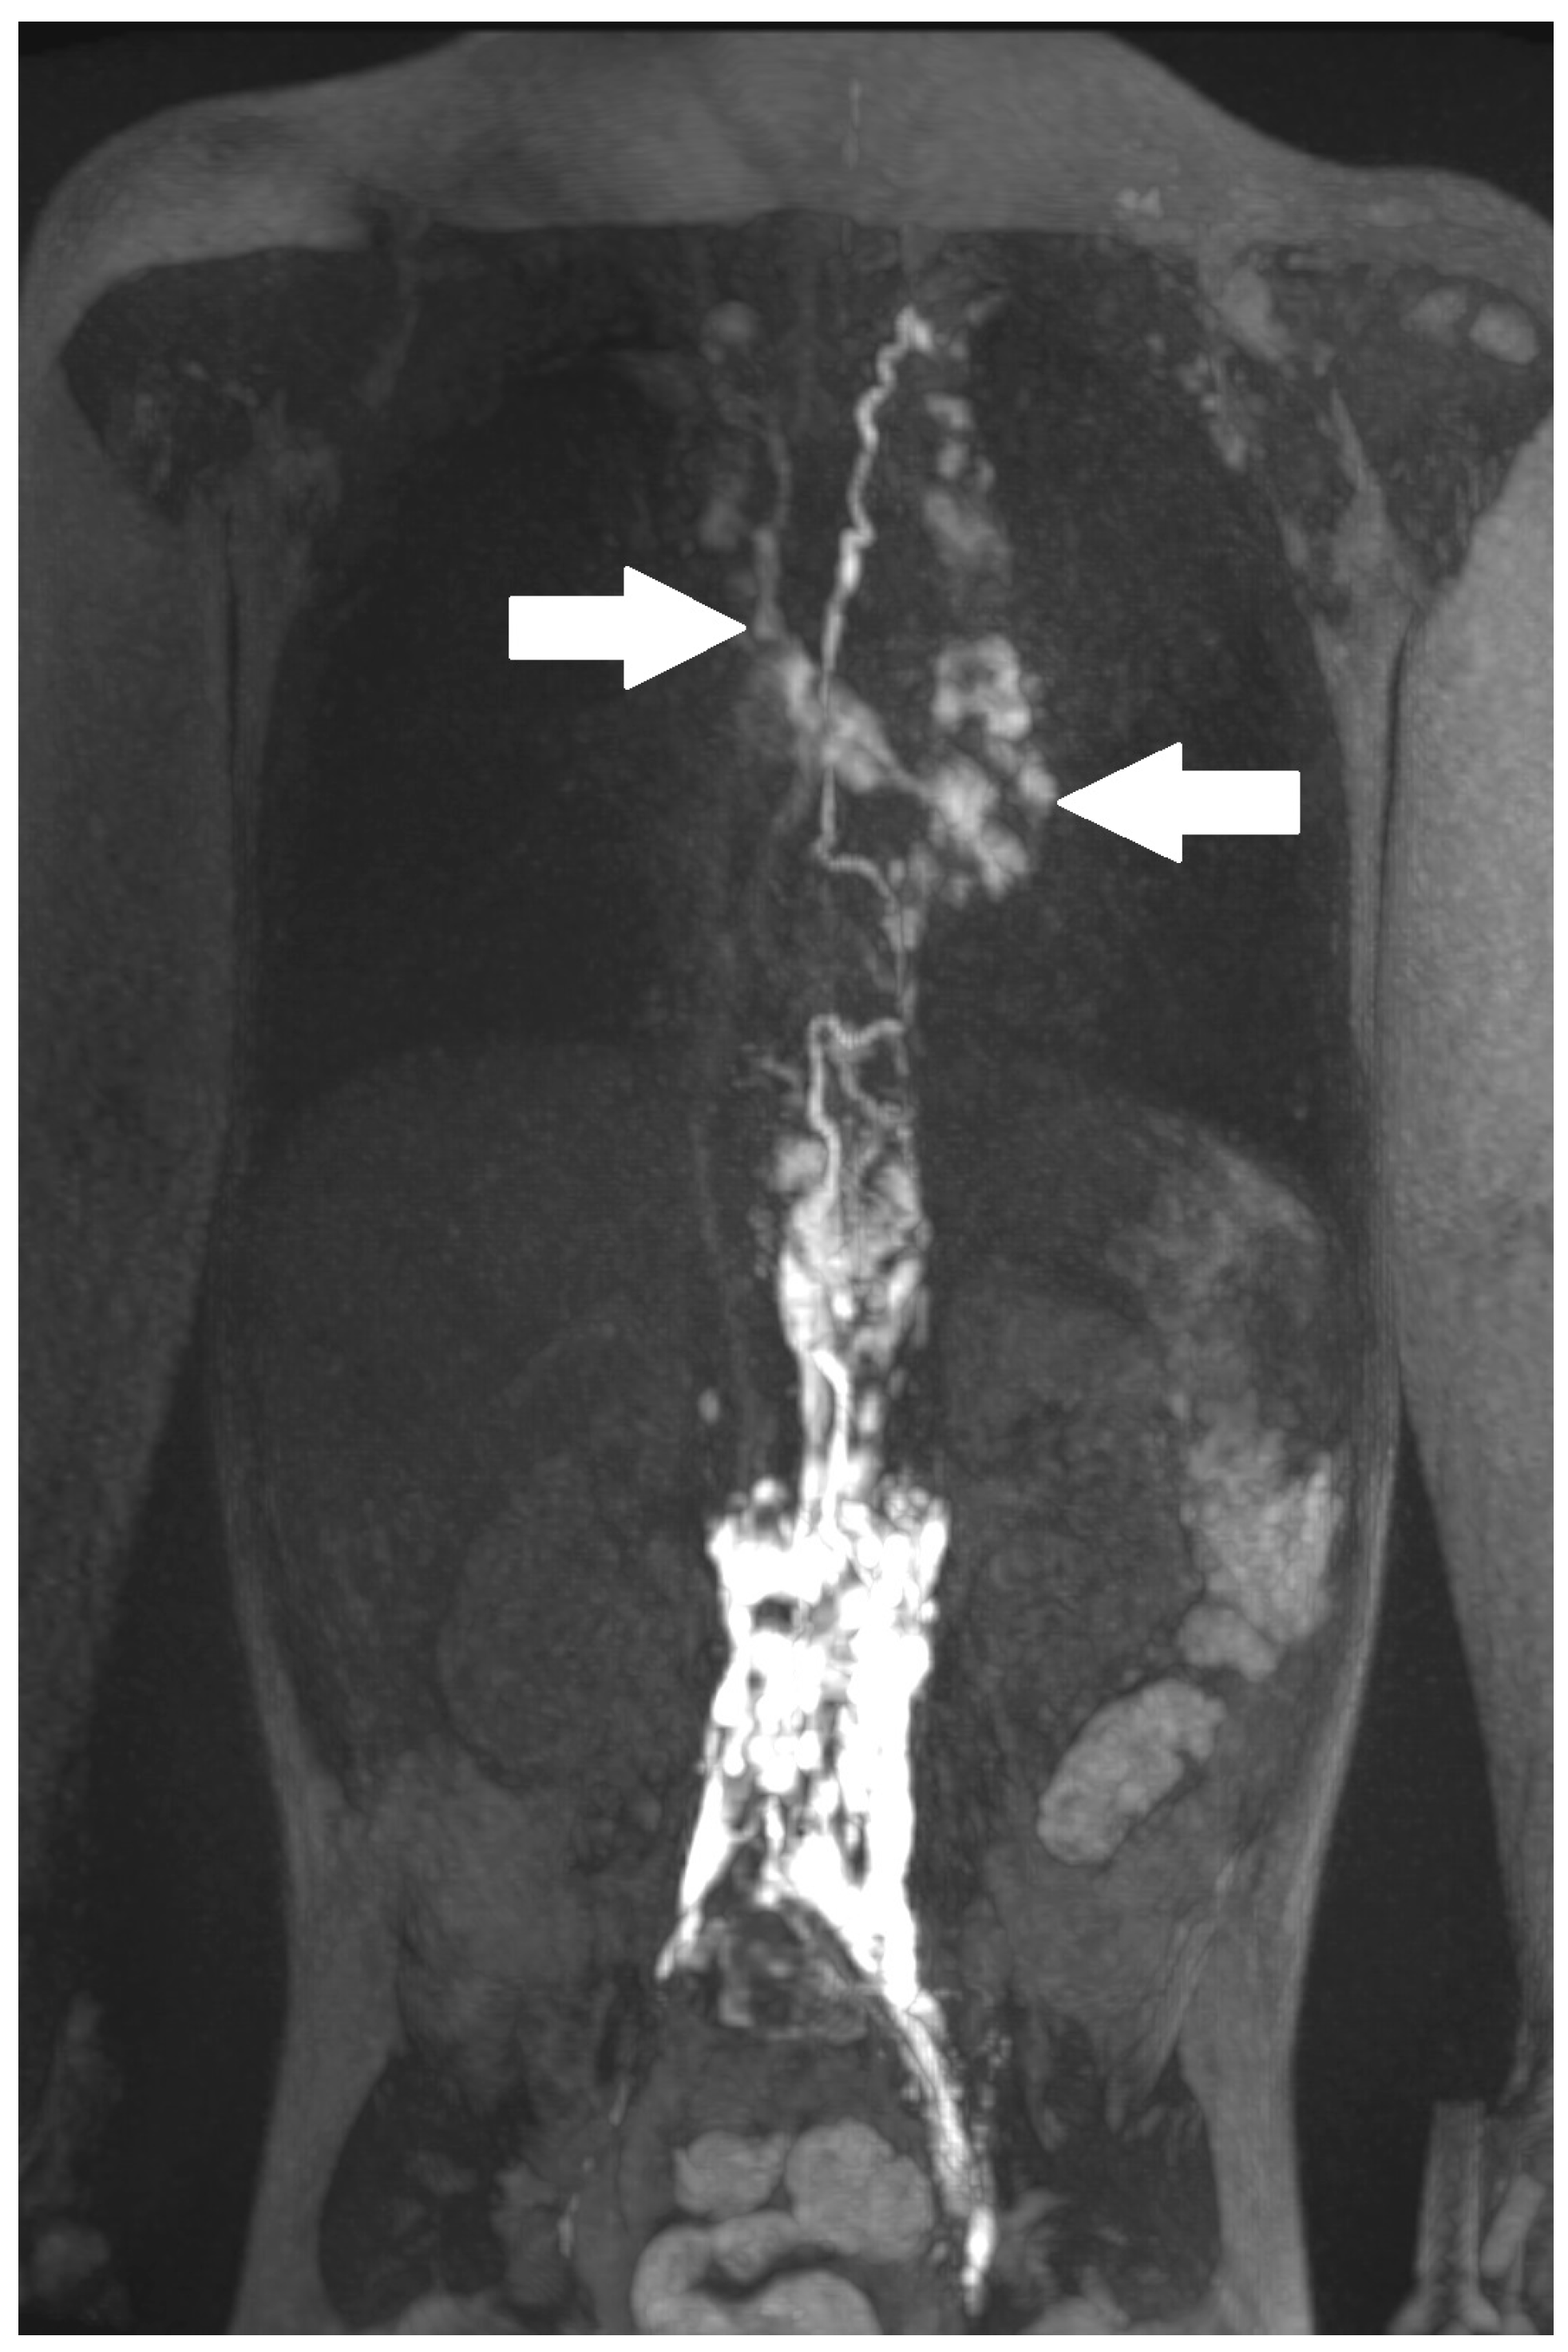

Figure 5.

Central lymphatic flow disorders: abnormal central lymphatic flow, effusion in more than one compartment (a, arrows point to thoracic compartment) and the presence of dermal backflow (b, see arrows, * shows a stop in contrast movement).

Postoperative chylothorax was classified as previously introduced by Dori et al. based on dynamic contrast MR lymphangiography and intranodal lymphangiography and are described as traumatic leak (Figure 3), pulmonary lymphatic perfusion syndrome (abnormal pulmonary lymphatic flow from the thoracic duct toward the lung parenchyma through abnormal lymphatic networks in the chest and/or lymphatic perfusion of the mediastinum) (Figure 4) or central lymphatic flow disorders (abnormal central lymphatic flow, effusion in more than one compartment and the presence of dermal backflow) (Figure 5a,b) [9].